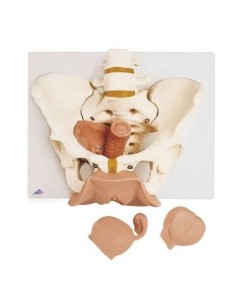

3B Modèle anatomique scientifique du bassin gravide, décomposable en 3 parties L20

Modèle anatomique du squelette du bassin d'un homme 3B Scientific H21/1

3B Bassin scientifique, anatomique Modèle pour illustrer l'accouchement L30